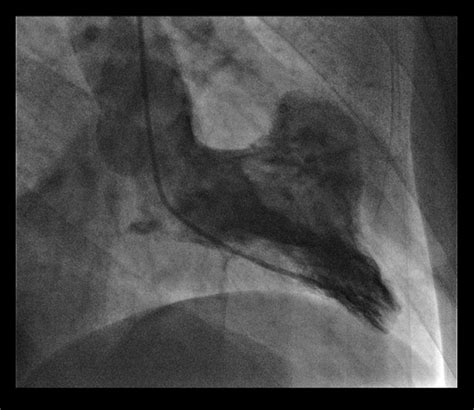

Understanding the complexities of cardiovascular health is crucial for maintaining overall well-being. One condition that often goes unnoticed until it becomes severe is a Left Ventricular Aneurysm. This condition affects the heart's left ventricle, which is responsible for pumping oxygen-rich blood to the rest of the body. A Left Ventricular Aneurysm occurs when a portion of the left ventricle's wall weakens and bulges outward, often as a result of a previous heart attack or other cardiac issues. This bulge can impair the heart's ability to pump blood efficiently, leading to various complications.

A Left Ventricular Aneurysm is a localized dilation of the left ventricle, typically caused by damage to the heart muscle. This damage is often the result of a myocardial infarction, commonly known as a heart attack. During a heart attack, blood flow to a part of the heart is blocked, leading to the death of heart muscle cells. Over time, the weakened area can bulge outward, forming an aneurysm.

• Echocardiogram: This uses sound waves to create images of the heart, allowing doctors to visualize the aneurysm and assess its size and location.

• Cardiac Catheterization: This invasive procedure involves inserting a catheter into the heart to measure pressure and blood flow, and to visualize the coronary arteries.